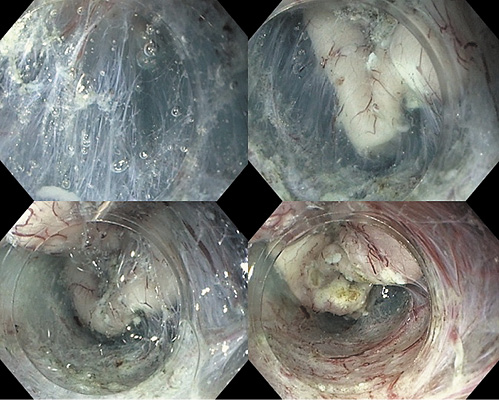

A 64-year-old woman, without relevant medical history, was referred to our department due to a 5-cm adenoma in the distal part of the second portion of the duodenum (Fig. 1). Due to the instability of the endoscope, the lesion size and localization, a complete resection by piecemeal-EMR was unlikely. Therefore, ESD was offered.

We used hydroxyethylamide with methylene blue for submucosal injection, and dual- and IT-nano knives (Olympus, Tokyo) for submucosal dissection. We started in the oral side by a small incision in the mucosa and then performed underwater ESD using a total of nearly 1 L of saline, creating a pocket beneath the lesion, with the uneventful en bloc resection of the entire lesion.

One of the major challenges in duodenal ESD is the absence of the contraction of the lesion after mucosal incision, which prevents an easy access to submucosa; at the same time, the muscle layer is very thin and the submucosal injection does not last long. Underwater technique allowed us to have an easier access to the submucosa, by pushing the mucosal flap away from the scope, and providing a clean visualization during the entire procedure. Once in the submucosa, pocket technique [1] allowed us to have a better scope stabilization throughout the procedure (Fig. 2); after dissecting the submucosa, we finished by cutting the remaining mucosa circularly.